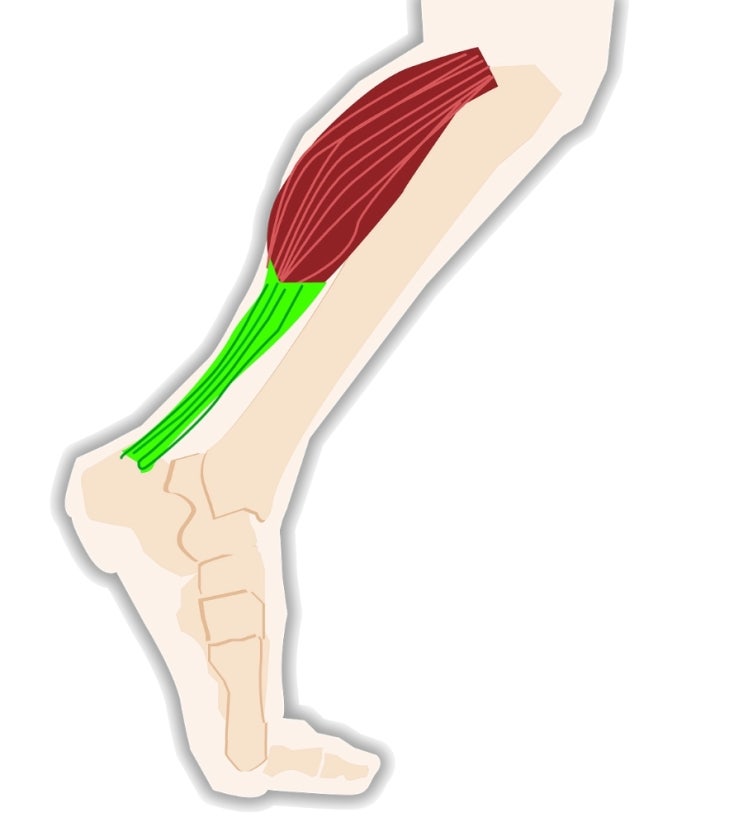

많은 사람들이 피로를 풀기 위해 종아리 마사지기를 사용하곤 하는데, 하지정맥류가 있는 사람이라면 주의해야 할 점이 많아요! ️ ‘제2의 심장’ 종아리 종아리는 ‘제2의 심장’이라고 불릴 만큼 혈액순환에 중요한 역할을 해요.

운동 후나 하루 종일 다리가 붓고 피곤할 때 종아리 마사지를 하면 혈액순환을 돕고 피로를 풀 수 있답니다. 하지만 잘못 사용하면 오히려 건강에 해로울 수 있어요.

특히 고령자나 신경이 약한 사람은 강한 압력에 주의해야 해요! 하지정맥류가 있다면 사용 금지 출처 아산병원 하지정맥류가 있는 사람은 마사지기를 사용하지 않는 것이 좋습니다.

종아리 마사지기의 강한 압력이 이미 약해진 혈관을 더 손상시킬 수 있기 때문이에요. 출처 백세시대 혈관에 있던 혈전이 떨어져 뇌경색 같은 ...